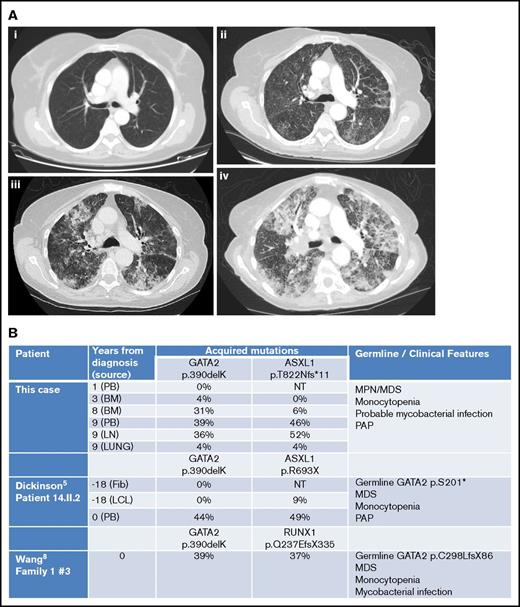

However, by then, she reported weight loss, worsening cough with breathlessness, and dystrophic nails consistent with fungal infection. Chest computed tomography revealed progressive changes with interstitial thickening and air space shadowing throughout both lungs, plus small volume necrotic mediastinal lymphadenopathy (Figure 2A). Sputum, BAL, and endobronchial ultrasound biopsies of her central lymphadenopathy were culture negative; lymph node histology showed acute necrotic changes. BAL contained branching hyphae consistent with Aspergillus species. BAL galactomannan was positive at 1.58, and voriconazole was commenced.

Imaging and molecular investigations. (A) Serial computed tomography chest images (2007-2015). (i) June 2007: no respiratory symptoms. Normal imaging. (ii) January 2015: no respiratory symptoms but evidence of progressive MPN/MDS. Early interstitial changes are present. (iii) June 2015: cough and breathlessness. Progressive interstitial changes plus air space shadowing are present. (iv) September 2015: respiratory failure secondary to PAP. “Crazy paving” changes plus consolidation characteristic of PAP visible. (B) Comparison of somatically acquired c.1168_1170delAAG p.390delK GATA2 mutations. Three patients have been reported with somatically acquired p.390delK mutation in GATA2. Germ line mutations in GATA2 and other cooperating mutations in ASXL1 or RUNX1 were also present in two previous cases. Fib, fibroblast; LCL, lymphoid cell line; LN, lymph node; NT, not tested; PB, peripheral blood.

Imaging and molecular investigations. (A) Serial computed tomography chest images (2007-2015). (i) June 2007: no respiratory symptoms. Normal imaging. (ii) January 2015: no respiratory symptoms but evidence of progressive MPN/MDS. Early interstitial changes are present. (iii) June 2015: cough and breathlessness. Progressive interstitial changes plus air space shadowing are present. (iv) September 2015: respiratory failure secondary to PAP. “Crazy paving” changes plus consolidation characteristic of PAP visible. (B) Comparison of somatically acquired c.1168_1170delAAG p.390delK GATA2 mutations. Three patients have been reported with somatically acquired p.390delK mutation in GATA2. Germ line mutations in GATA2 and other cooperating mutations in ASXL1 or RUNX1 were also present in two previous cases. Fib, fibroblast; LCL, lymphoid cell line; LN, lymph node; NT, not tested; PB, peripheral blood.

She was investigated for the presence of GATA2 mutation. BM DNA was extracted from paraffin blocks using the QIAamp DNA FFPE Tissue Kit (56404; QIAGEN) according to the manufacturer’s instructions. Using Sanger sequencing, the patient was found to harbor a mutation in exon 8 of GATA2 (c.1168_1170delAAG; p.390delK) and a mutation of ASXL1 (c.2464_2465insA; p.T822Nfs*11). The GATA2 mutation was predicted to be disease-causing using the MutationTaster prediction program6 (Mutation Surveyor software version 4.0.8). On retrospective analysis of her previous DNA samples and estimation of variant allele frequency from electrophoretograms, this GATA2 mutation was not detected in 2006, increased in abundance from 2009 to 2015, and was only found at 4% in lung tissue in 2015, suggesting that it was an acquired somatic mutation (Figure 2B; supplemental Figures). ASXL1 mutation was observed emerging at later time points, probably as a subclone.

Somatic mutations in GATA2 occur rarely in MPN and other myeloid neoplasms,9,11-13 with the exception of MDS/AML associated with biallelic CEBPA mutations.7 Our patient had a trinucleotide deletion c.1168_1170delAAG; p390delK, identical to that previously reported as a second somatic mutation in 2 other patients with coexisting germ line GATA2 mutations (Figure 2B). In our previous patient (14.II.2),5 p390delK was confirmed as somatic by serial sampling and sequencing of fibroblast and LCL DNA. In the other reported patient, p390delK was proven to be biallelic with the germ line GATA2 mutation by TA-cloning.12 In all three, cooperating ASXL1 or RUNX1 mutations were observed at similar variant allele frequency to the somatic GATA2 variant. The present case remains unique in that an isolated somatic GATA2 mutation was responsible for the GATA2-related disease.